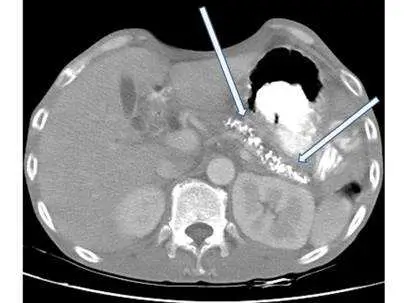

一名酗酒男性因上腹悶痛和食慾不佳來求診,電腦斷層檢查呈現如圖,箭號所指之異常最可能是下列那一項診斷?

本題 CT 影像為腹部橫截面,兩支箭號指向胃後方(pancreatic body/tail 區域)多發、散在分布的高密度白色鈣化灶(bright hyperdense foci)。具體所見如下:

- 鈣化位置:位於胃(黑色含氣腔)後方、腹腔中央,解剖位置對應胰臟本體至尾部

- 鈣化特徵:多發性、不規則點狀至粗顆粒狀高密度影,CT 值接近骨骼密度,為典型的胰臟內鈣化(intraductal / parenchymal calcifications)

- 周圍結構:肝臟(右側)、脾臟(左側)外觀尚可;無明顯游離氣體(排除腸穿孔);膽總管無明顯擴張;脾動脈無管壁鈣化形態

- 鑑別要點:這種散在分布於胰臟實質/導管的多發鈣化,與膽總管結石(單顆或少數、沿膽道走向)、腸穿孔(游離氣體)、或脾動脈動脈硬化(沿血管壁弧形鈣化)的影像特徵截然不同